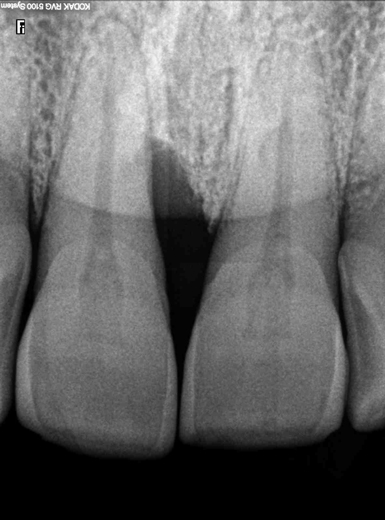

Η διάγνωση για τη νόσο (ουλίτιδα ή περιοδοντίτιδα), την έκτασή της (εντοπισμένη ή γενικευμένη σε όλο το στόμα) και τη βαρύτητά της (αρχόμενη, μέτριας ή προχωρημένης βαρύτητας), τίθεται μετά από κλινική και ακτινογραφική εξέταση.

Κατά τον ακτινογραφικό έλεγχο παρατηρούμε:

• Το βαθμό της απώλειας οστού

• Την κατάσταση στις περιοχές συμβολής των ριζών